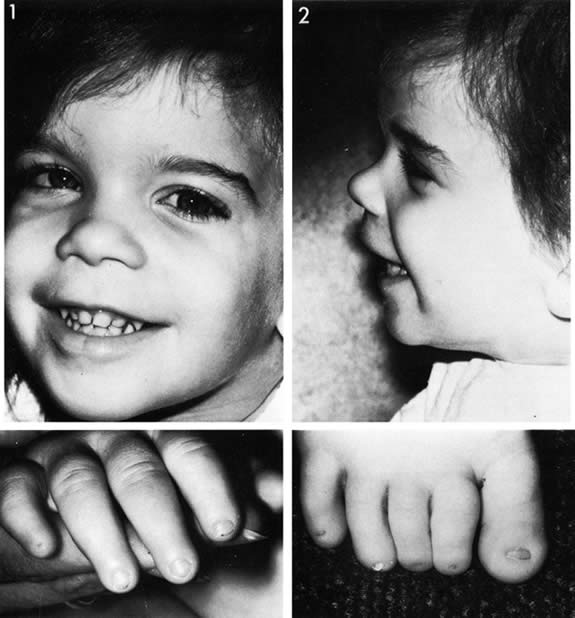

infants: A controlled trial. Pediatrics 79:61, 1987 224. Kushner BJ, Essner D, CohenIL , et al: Retrolental fibroplasia. Part II. Pathologic correlation. Arch Ophthalmol 95:29, 1977 225. Ashton N: Oxygen and the retinal blood vessels. Trans Ophthal Soc UK 100:359, 1980 226. Hittner HM, Rudolph AJ, Kretzer FL: Suppression of severe retinopathy of prematurity with vitamin E supplementation: Ultrastructural

mechanism of clinical efficacy. Ophthalmology 91:1512, 1984 227. Johnson L: Retrolental fibroplasia. A new look at an unsolved problem. Hosp Pract 16:109, 1981 228. Johnson L, Quinn GE, Abbas S, et al: Effect of sustained pharmacologic vitamin E levels on incidence and severity

of retinopathy of prematurity: A controlled clinical trial. J Pediatr 114:827, 1989 229. Johnson L, Quinn GE, Abbasi S, et al: Severe retinopathy of prematurity in infants with birth weights less than 1250 grams: Incidence

and outcome of treatment with pharmacologic serum

levels of vitamin E in addition to cryotherapy from 1985 to 1991. J Pediatr 127:632, 1995 230. Raju TN, Langenberg P, Bhutani V, et al: Vitamin E prophylaxis to reduce retinopathy of prematurity: a reappraisal

of published trails. J Pediatr 131:844, 1997 231. Law MR, Wijewardene K, Wald NJ: Is routine vitamin E administration justified in very low-birthweight

infants. Dev Med Child Neurol 32:442, 1990 232. Schaffer DB, Johnson L, Quinn GE, et al: Vitamin E and retinopathy of prematurity: Follow-up at one year. Ophthalmology 92:1005, 1985 233. Wender DF, Thulin GE, Wolken Smith GJ, et al: Vitamin E affects lung biochemical and morphologic response to hyperoxia

in the newborn rabbit. Pediatr Res 15:262, 1981 234. Saldanha RL, Cepeda EE, Poland RL: The effect of vitamin E prophylaxis on the incidence and severity of bronchopulmonary

dysplasia. J Pediatr 101:89, 1982 235. Arrowsmith JB, Faich GA, Tomita DK, et al: Morbidity and mortality among low birth weight infants exposed to an intravenous

vitamin E product, E-ferol. Pediatrics 83:244, 1989 236. Neal PR, Erickson P, Baenziger JC, et al: Serum vitamin E levels in the very low birth weight infant during oral

supplementation. Pediatrics 77:636, 1986 237. Ehrenkranz RA: Vitamin E and retinopathy of prematurity: Still controversial. J Pediatr 114:801, 1989 238. Cremer RJ, Perryman PW, Richards DH: Influence of light on the hyperbilirubinemia of infants. Lancet 1:1094, 1958 239. Brown AK, Kim MH, Wu PYK, et al: Efficacy of phototherapy in prevention and management of neonatal hyperbilirubinemia. Pediatrics 75:393, 1985 240. Ennever JF, Knox I, Denne SC, et al: Phototherapy for neonatal jaundice. In vivo clearance of bilirubin photoproducts. Pediatr Res 19:205, 1985 241. Landry RJ, Schedt PC, Hammond RW: Ambient light and phototherapy conditions of eight neonatal care units: A

summary report. Pediatrics 75:393, 1985 242. Rubaltelli FF, Zanardo V,0Granati B: Effect of various phototherapy regimens on bilirubin decrement. Pediatrics 61:838, 1978 243. Tan KL: The pattern of bilirubin response to phototherapy for neonatal hyperbilirubinemia. Pediatr Res 16:670, 1982 244. Dobson V: Phototherapy retinal damage. Invest Ophthalmol 15:595, 1976 245. Messner KH, Maisels MJ, Loure-DuPree AE: Phototoxicity to the newborn primate retina. Invest Ophthalmol Vis Sci 17:1178, 1978 246. Messner KH: Light toxicity to newborn retina. Pediatr Res I2:530, 1978 247. Sykes SM, Robison WG, Waxier M, et al: Damage to the monkey retina by broad-spectrum fluorescent light. Invest Ophthalmol Vis Sci 20:425, 1981 248. Kalina RE, Forrest GL: Ocular hazards of phototherapy for hyperbilirubinemia. J Pediatr Ophthalmol 8:116, 1971 249. Dobson V, Cowett RM, Riggs LA: Long-term effects of phototherapy on visual function. J Pediatr 86:555, 1975 250. Bhupathy K, Sethupathy R, Pildes RS, et al: Electroretinography in neonates treated with phototherapy. Pediatrics 61:189, 1978 251. Dobson V, Riggs L, Siqueland ER: Electroretinographic determination of dark adaptation functions of children

exposed to phototherapy as infants. J Pediatr 85:25, 1974 252. Sherman SM: Development of interocular alignment in cats. Brain Res 37:187, 1972 253. Cyander M, Berman N, Hein A: Recovery of function in cat visual cortex following prolonged deprivation. Exp Brain Res 25:139, 1976 254. Cyander M: Interocular alignment following visual deprivation in the cat. Invest Ophthalmol Vis Sci 18:726, 1979 255. Weisel TN, Hubel OH: Comparison of the effects of unilateral and bilateral eye closure on cortical

unit responses in kittens. J Neurophysiol 28:1029, 1965 256. Hubel DH: The visual cortex of normal and deprived monkeys. Am Sci 67:532, 1979 257. Drew JH: Phototherapy: Short- and long-term complications. Arch Dis Child 51:454, 1976 258. Hoyt CS: The long-term visual effects of short-term binocular occlusion